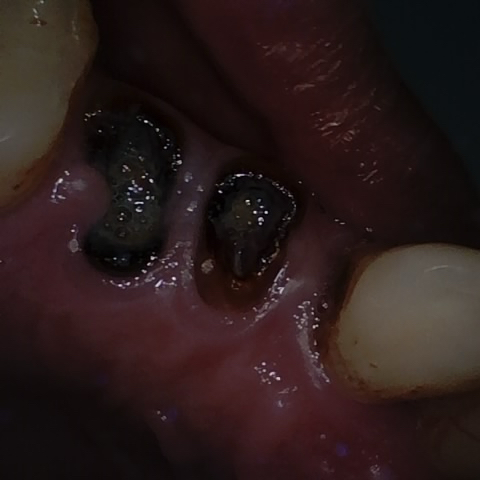

NHD36692

Annotated as "Good"